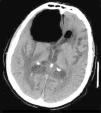

Spontaneous pneumocephalus following cerebrospinal fluid shunt is a rare complication. In most cases, the air enters in the intracranial cavity via a skull base defect. We report 2 cases of delayed tension pneumocephalus, secondary to ventriculoperitoneal shunt, and review the etiopathogenesis, prevention and treatment of this condition.